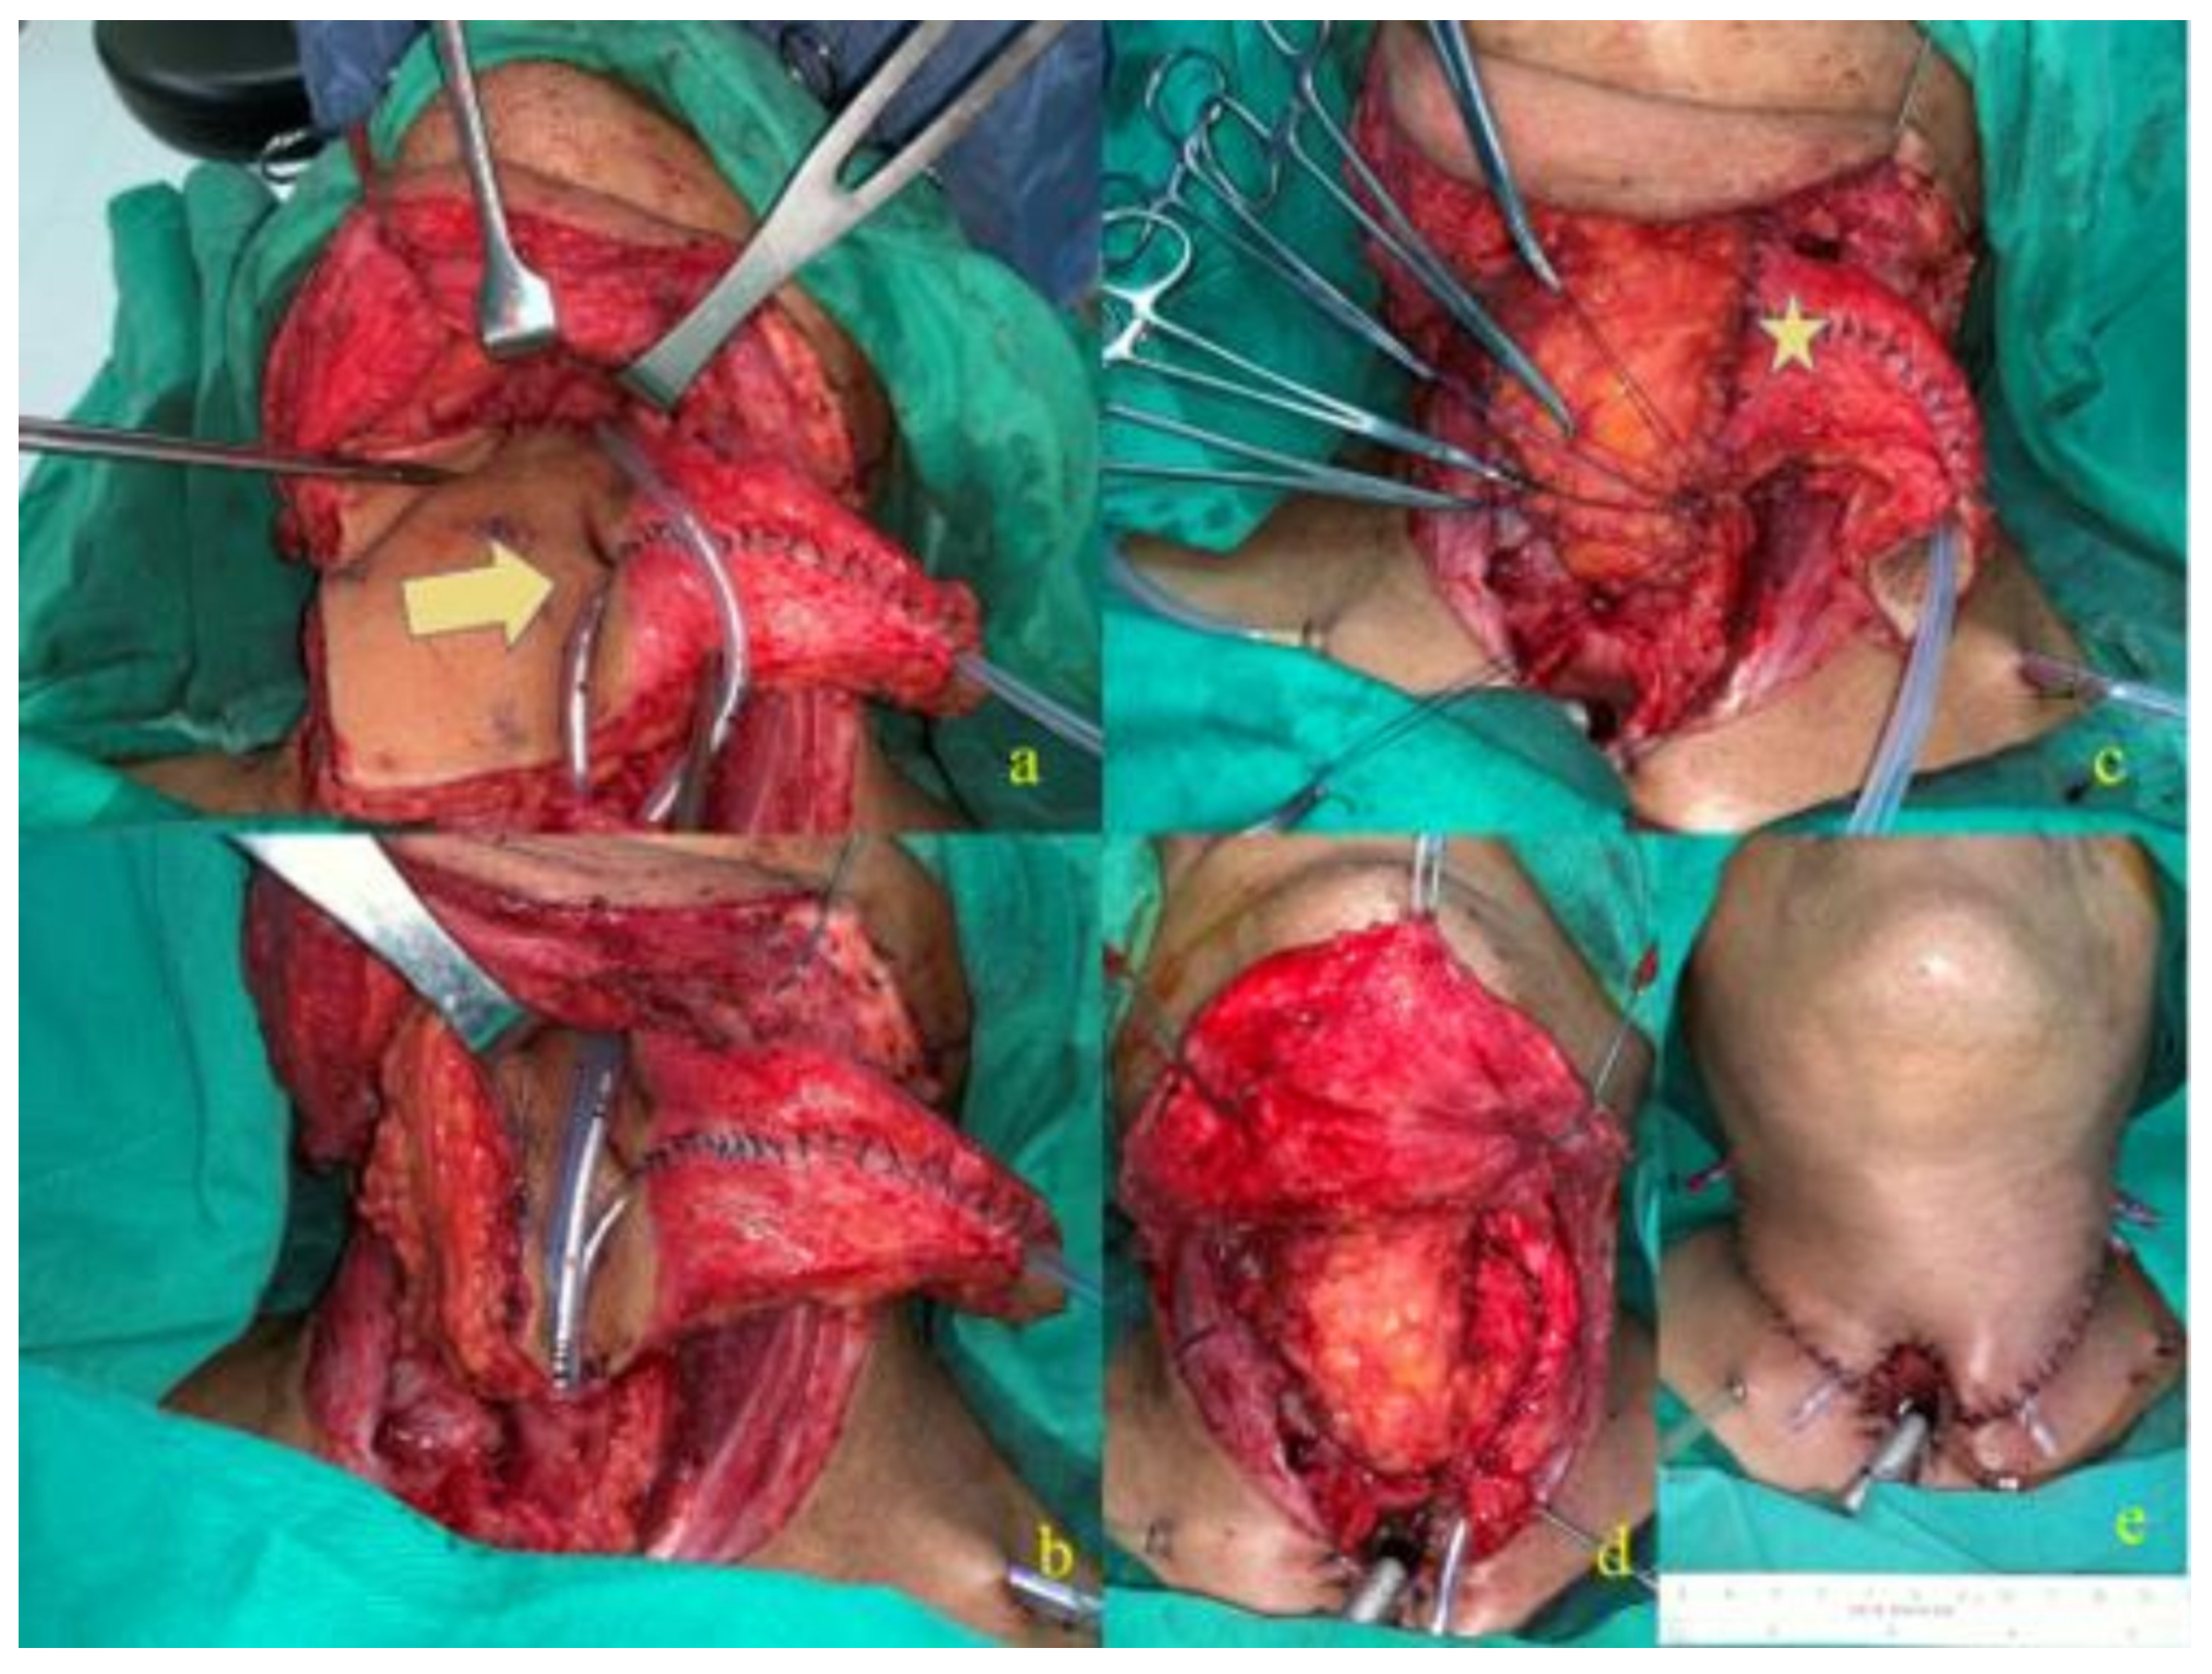

2.1. Surgical Technique

2.1.1. Tracheoesophageal Puncture

2.1.2. J-Flap Phonatory Tube